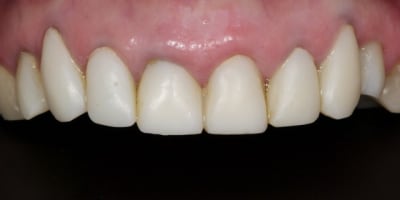

La suite avec les deuxièmes provisoires en places, le projet esthétique étant validé, les emp. ont été réalisées, ceramo-metal sur moignon composite a venir..

Bravo,

Très beau cas.

Une photo des préparations aurait été utile pour comprendre le choix des matériaux pour les CCM ou CCC.

Notamment pour la 21 qui me semble un peu grise avec la provisoire sur l'angle mésio vestibulaire.

En ce qui concerne le choix entre ccc et ccm, il faut savoir que 90 % de mes couronnes sont en emax, mais dans le cas de racines extrêmement colorées ( ce qui est le cas ici)mon choix se porte sur des ccm classiques pour masquer ces colorations radiculaires que même une chape opaque sur emax ne peux dissimuler aussi bien qu'une ccm.